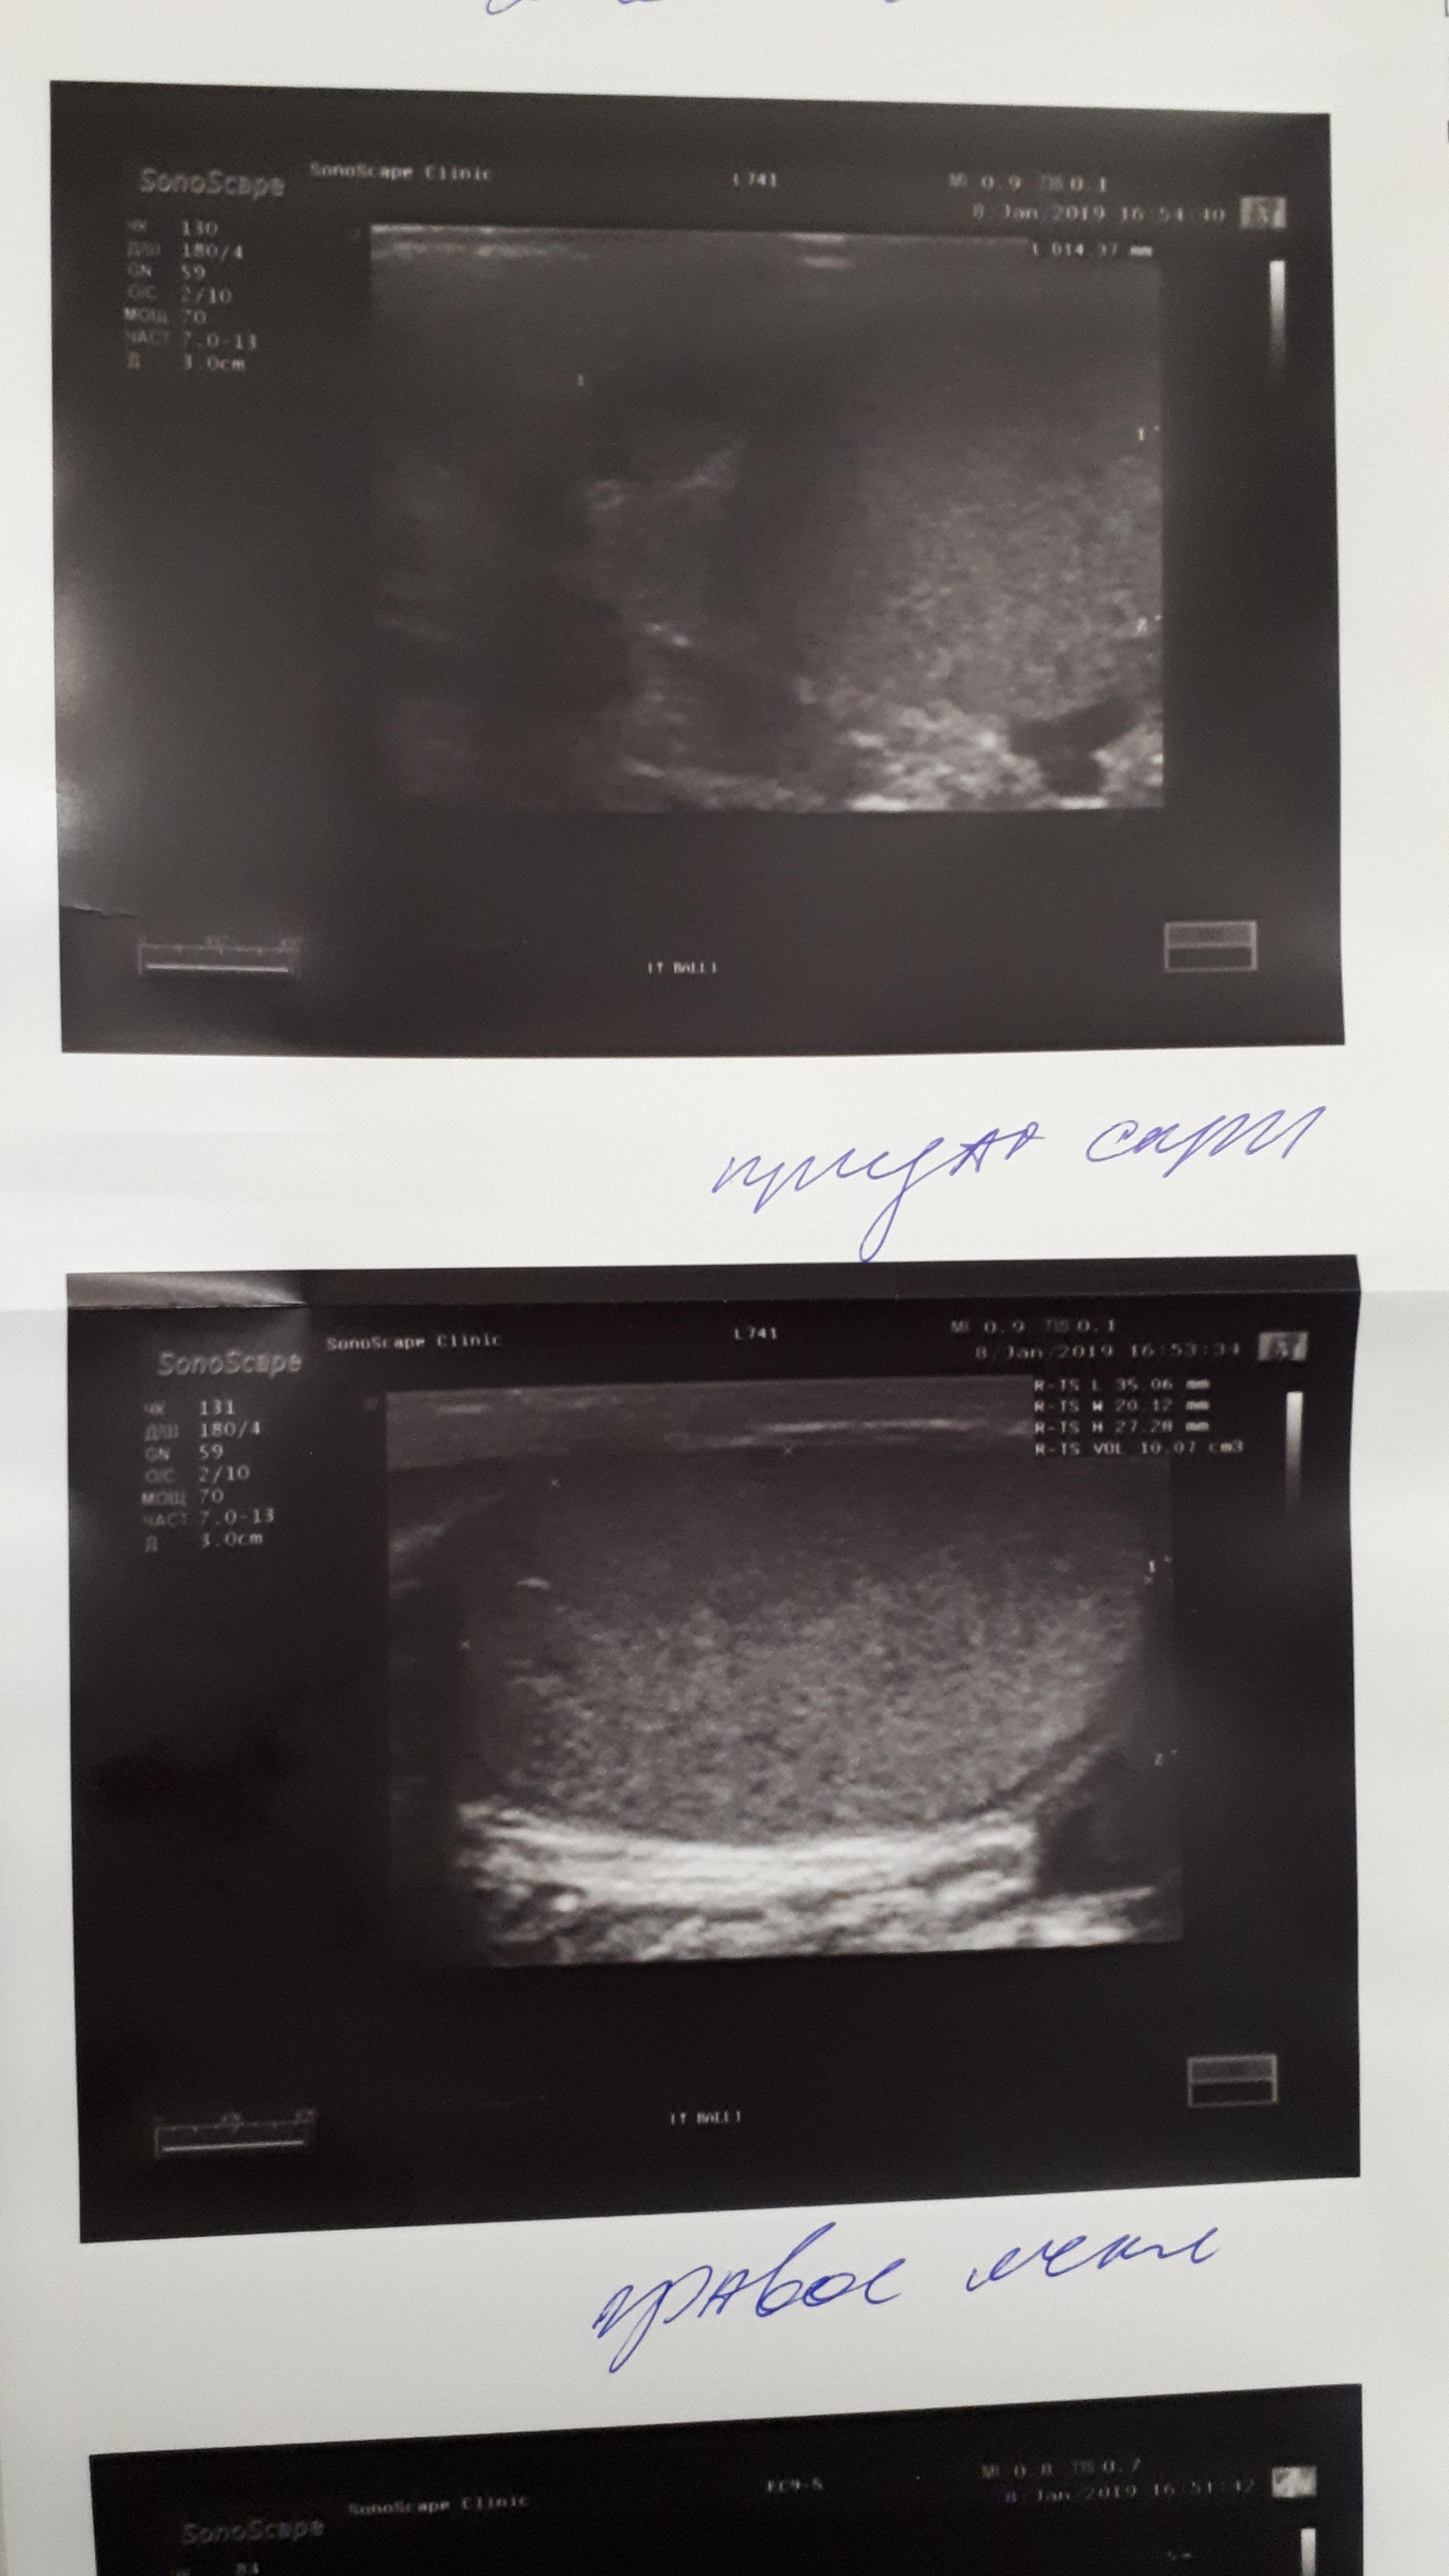

здравствуйте, периодически беспокоят боли в правом яичке, обращался к трём урологам, сдавал на разные инфекции , ничего нет, по УЗИ поставили диагноз хр. эпидидимит, после назначенного не заметил сильного улучшения, боли возвращаются, последний врач к которому обратился сказал будут боли , свечи вольтарен и все. Есть ли лечение при обострении этой болезни? Как мне самому кажется первые боли появились после не сильного удара по правому яичку.